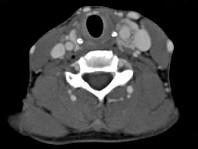

问题 女,39岁,左颈部可扪及一肿块,无发热,无疼痛,CT如图所示,最可能的诊断是()

选项 A.颈部神经鞘瘤 B.颈动脉体瘤 C.颈部神经纤维瘤 D.颈部海绵状血管瘤 E.颈动脉瘤

答案 B